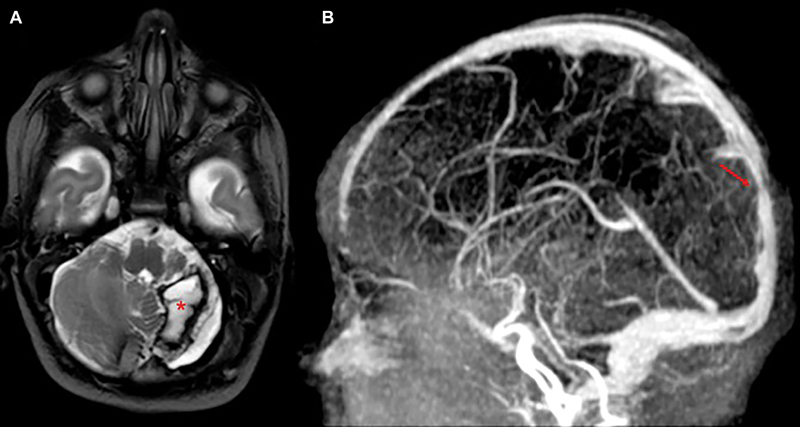

Results: Heparin therapy was started shortly after diagnosis, without hemorrhagic complications. Neuroimaging showed complete thrombus resolution. The neonate had a normal neurological examination at discharge. Follow-up confirmed overall good clinical condition and showed mild axial hypotonia and convergent strabismus suggestive of cortical visual impairment.

Conclusion: Management of CSVT in neonates remains debated. While heparin may carry a risk of bleeding, delaying treatment can lead to thrombus progression. Our case supports the potential safety and efficacy of early heparin use in selected patients. Tailored, risk-based decisions may improve outcomes, though further studies are needed to establish standardized protocols.